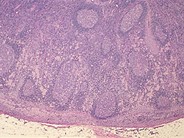

Toxoplasmosis - 5.

Category: Reactive Marrow > Reactive changes